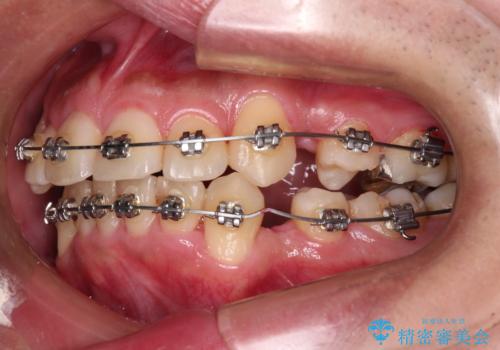

- メタルブラケット

右上第一小臼歯は歯根癒着により移動せず、左上第二小臼歯は移動はするものの非常に動きが鈍かったため、抜歯したスペースを閉じるまでに非常に時間がかかってしまいました。

患者様には辛抱強く治療にお付き合いいただき、すっきりとした口元に仕上げることができました。